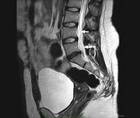

Diagnostic & Treatment Delay in Temporal Lobe Epilepsy

Rajarshi Mazumder, MD; Jessica Pasqua, MDRajarshi Mazumder, MD; Jessica Pasqua, MD - Imaging & Testing